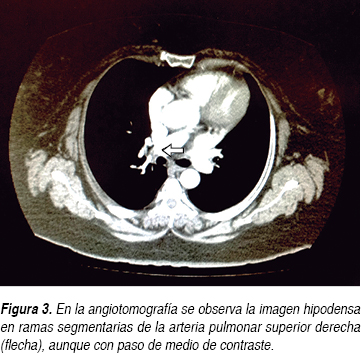

Durante su estancia hospitalaria la paciente presentó mejoría clínica, disminuyendo las cifras de presión arterial a valores normales tras ajustar el tratamiento antihipertensivo con losartán, nifedipino de liberación prolongada, nitratos orales, hipolipemiantes orales, sulfonilurea y metformina. Se incrementó la dosis de warfarina desde su ingreso a piso. Posteriormente, tras la desaparición del dolor subesternal y con la disminución de la disnea, se le pidió una ecografía de cuatro extremidades para ser realizada en un hospital de tercer nivel, sin embargo, sólo se reportó la ecografía Doppler color con enfoque en sistema venoso de miembros inferiores, sin documentarse anormalidades significativas que indicaran trombosis venosa profunda (TVP) en miembros inferiores; aunque cabe aclarar que clínicamente no presentaba dolor o datos sugestivos de tromboflebitis en extremidades superiores. Posteriormente se le solicitó a la paciente una angiotomografía de arteria pulmonar (Figuras 3 y 4), donde se demostró la presencia de un trombo (infarto pulmonar) en las ramas segmentarias de la arteria pulmonar superior derecha con datos de canalización parcial y sin imagen de semiluna, la cual orientó a pensar en un trombo crónico. No se reportaron anormalidades en el FVCI (Figura 5). La paciente fue egresada por mejoría clínica cinco días después de su hospitalización y la relación internacional normalizada (INR) a su egreso hospitalario se reportó en 3.5.